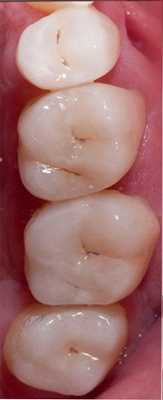

На рисунке 1 показана исходная ситуация.Классический фиссурный кариес зубов 16 и 17. Как и в большинстве подобных случаев, кариозный процесс протекает абсолютно бессимптомно.

Окклюзионная коррекция, как правило, минимальна или вообще отсутствует. Вид реставраций через двое суток (рис. 11) .